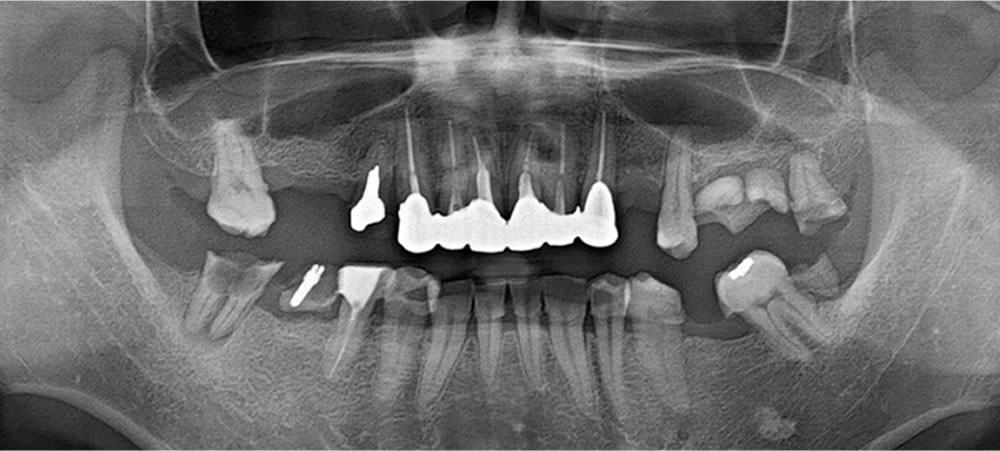

初診時の口腔内

口腔内は全顎崩壊している状態で、すぐにでも抜歯をしたほうがよい状態の歯が多数ありました。痛みも伴っていることから、まずは痛みの改善が最優先事項と考え、必要部位の抜歯を治療計画立案に先立って行いました。